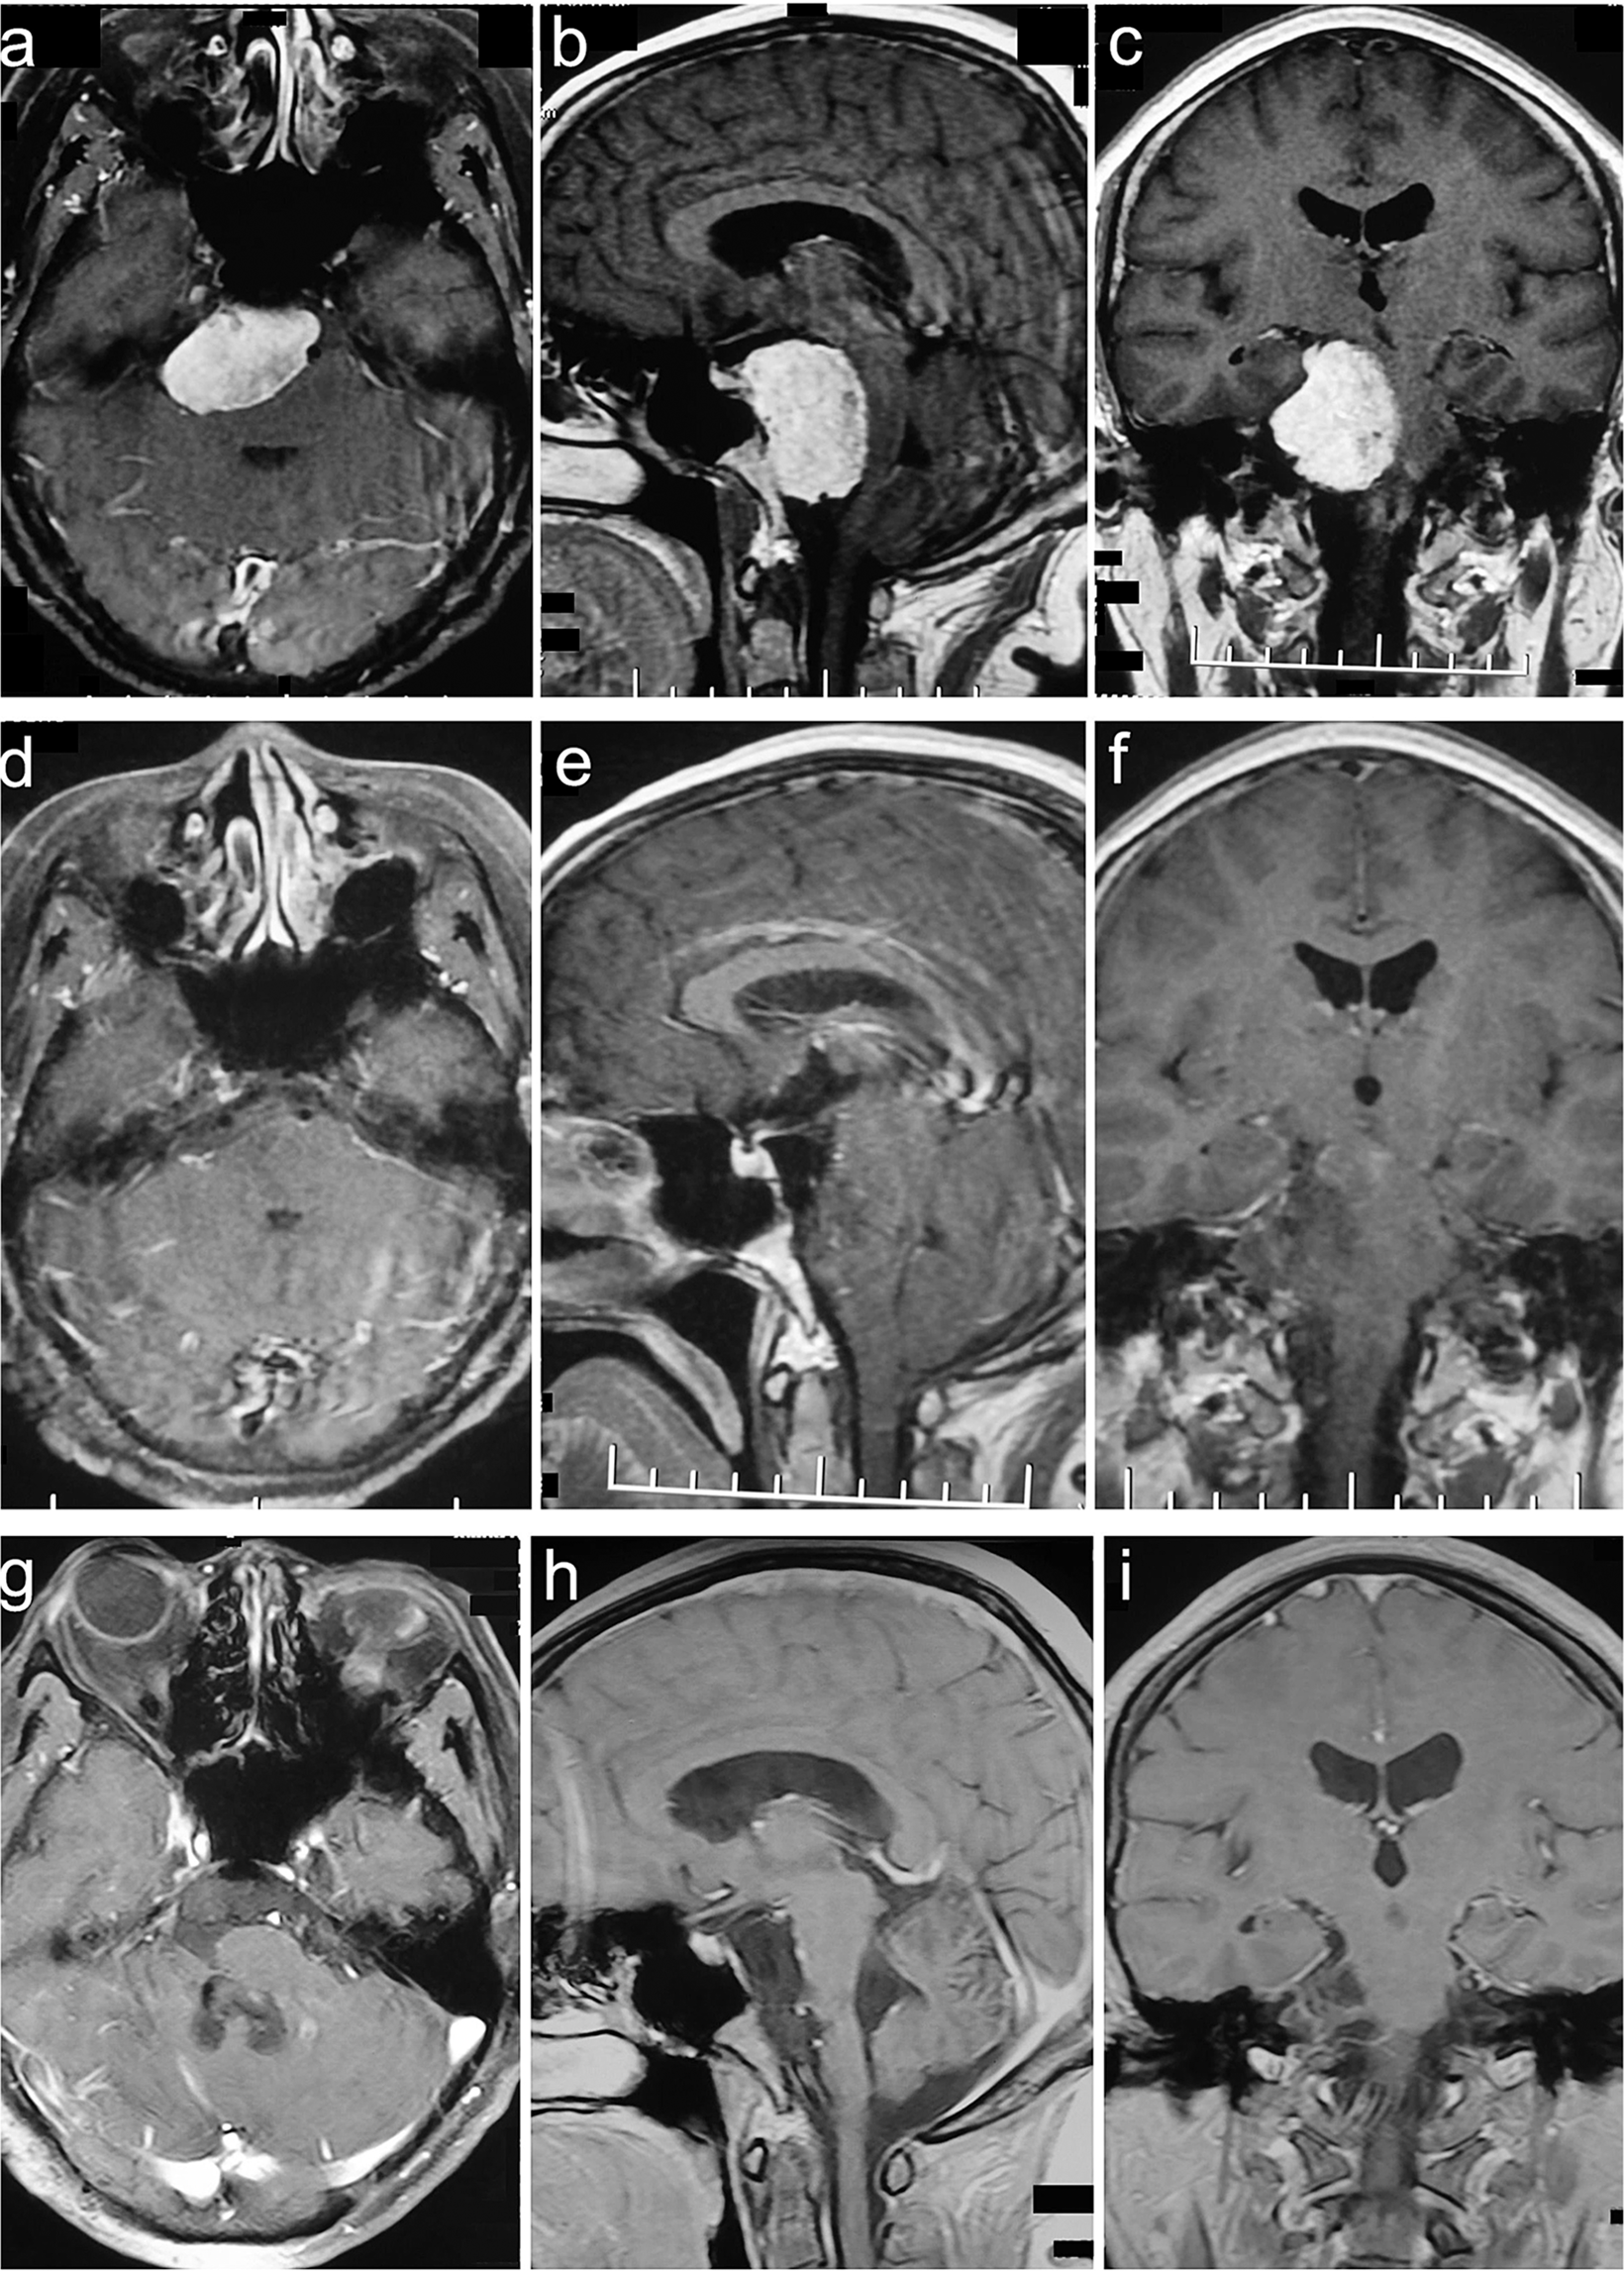

Figure 2

Clivus type case. A 56-year-old female presented with headache, dysphagia, bucking and hearing impairment for 84 months. The preoperative KPS score was 80. She was achieved GTR with the RSA of palsy in CN V and VII. The postoperative KPS score was 50. With a follow-up of 75 months, she participated in normal activities and had a KPS score of 90 without recurrence. (a–c) Preoperative MRI T1 contrast axial, sagittal, and coronal images. (d–f) Postoperative MRI T1 contrast axial, sagittal, and coronal images. (g–i) Follow-up MRI T1 contrast axial, sagittal, and coronal images.